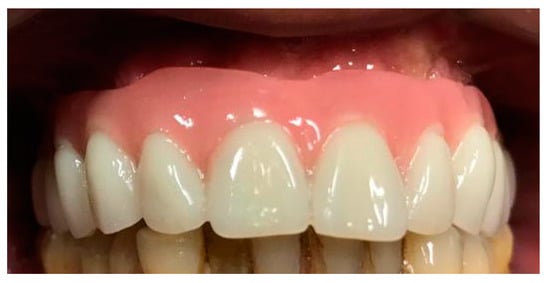

3.1. SCAI Approach Clinical Case